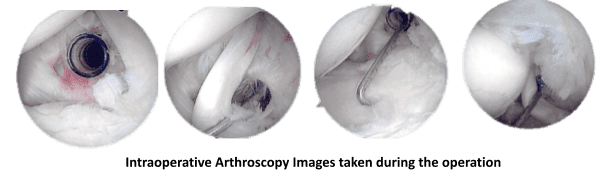

El drapeado se hacía en el hombro izquierdo, y la extremidad superior izquierda colgaba sobre una polea con un peso de 10 libras. Se creó una puerta posterior para permitir una pequeña incisión a lo largo de la articulación glenohumeral posterior y la introducción de un endoscopio.

El portal anterior se creó mediante localización de la aguja espinal, incisión y un trocar. La articulación glenohumeral mostró osteoartritis de la cabeza húmeral de grado 3 a grado 4, con colgajos de cartílago y deshilacho del labrum. Se pudo identificar una ruptura de grosor parcial de alto grado del infraespinoso detrás del tendón del bíceps.

Los colgajos condrales sueltos fueron afeitados y el labrum fue desbridado. Se pasaba un PDS sobre una aguja espinal a través del desgarro del manguito rotador para localizar. El desbridamiento del colgajo de cartílago se realizó a través del portal de trabajo posterior. Había bursitis extensa, se extirpó el subacromial y se realizó una bursectomía.

El acromion fue reparado y se realizó una acromioplastia. Identificado el PDS, se preparó la rotura del manguito rotador y el hueso fue desgastado. El portal posterolateral se hizo en línea con el desgarro para el paso de suturas hacia el manguito rotador desde un ancla y se ató con un nudo. El nudo se ató desde un portal superior.

Se hicieron las fotos finales y el hombro fue drenado. Los portales se cerraron con nylon. El vendaje se hizo con Adaptic, 4×4, ABD y cinta adhesiva. El paciente fue trasladado a la zona de detención postoperatoria. El paciente toleró bien el procedimiento.